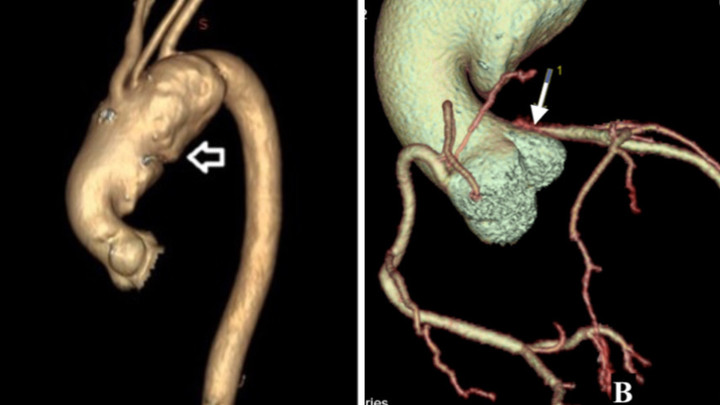

Hình ảnh trước mổ: A – khối phồng động mạch chủ rất lớn; B – Động mạch vành trái tắc hoàn toàn. (Ảnh: BVCC)

TS.BS Vũ Ngọc Tú, phẫu thuật viên chính thực hiện ca mổ cho biết khối phình động mạch chủ khổng lồ là căn nguyên chính chèn ép gây tắc động mạch vành trái, hở van hai lá nhiều, giãn lớn và giảm nặng chức năng co bóp của cơ tim, dẫn đến triệu chứng khó thở, khiến người bệnh phải đi khám bệnh.

GS.TS Nguyễn Lân Việt, Chủ tịch Hội Tim mạch Việt Nam - nguyên Hiệu trưởng trường Đại học Y Hà Nội - người trực tiếp tham chữa trị cho bệnh nhân nhận định đây là trường hợp hiếm gặp trong y học. Hình ảnh siêu âm tim và chụp cắt lớp vi tính cho thấy khối phình động mạch chủ rất lớn có đường kính lên đến gần 10cm (kích thước bình thường là dưới 3cm, nếu từ 5,5cm trở lên thì cần phải phẫu thuật).